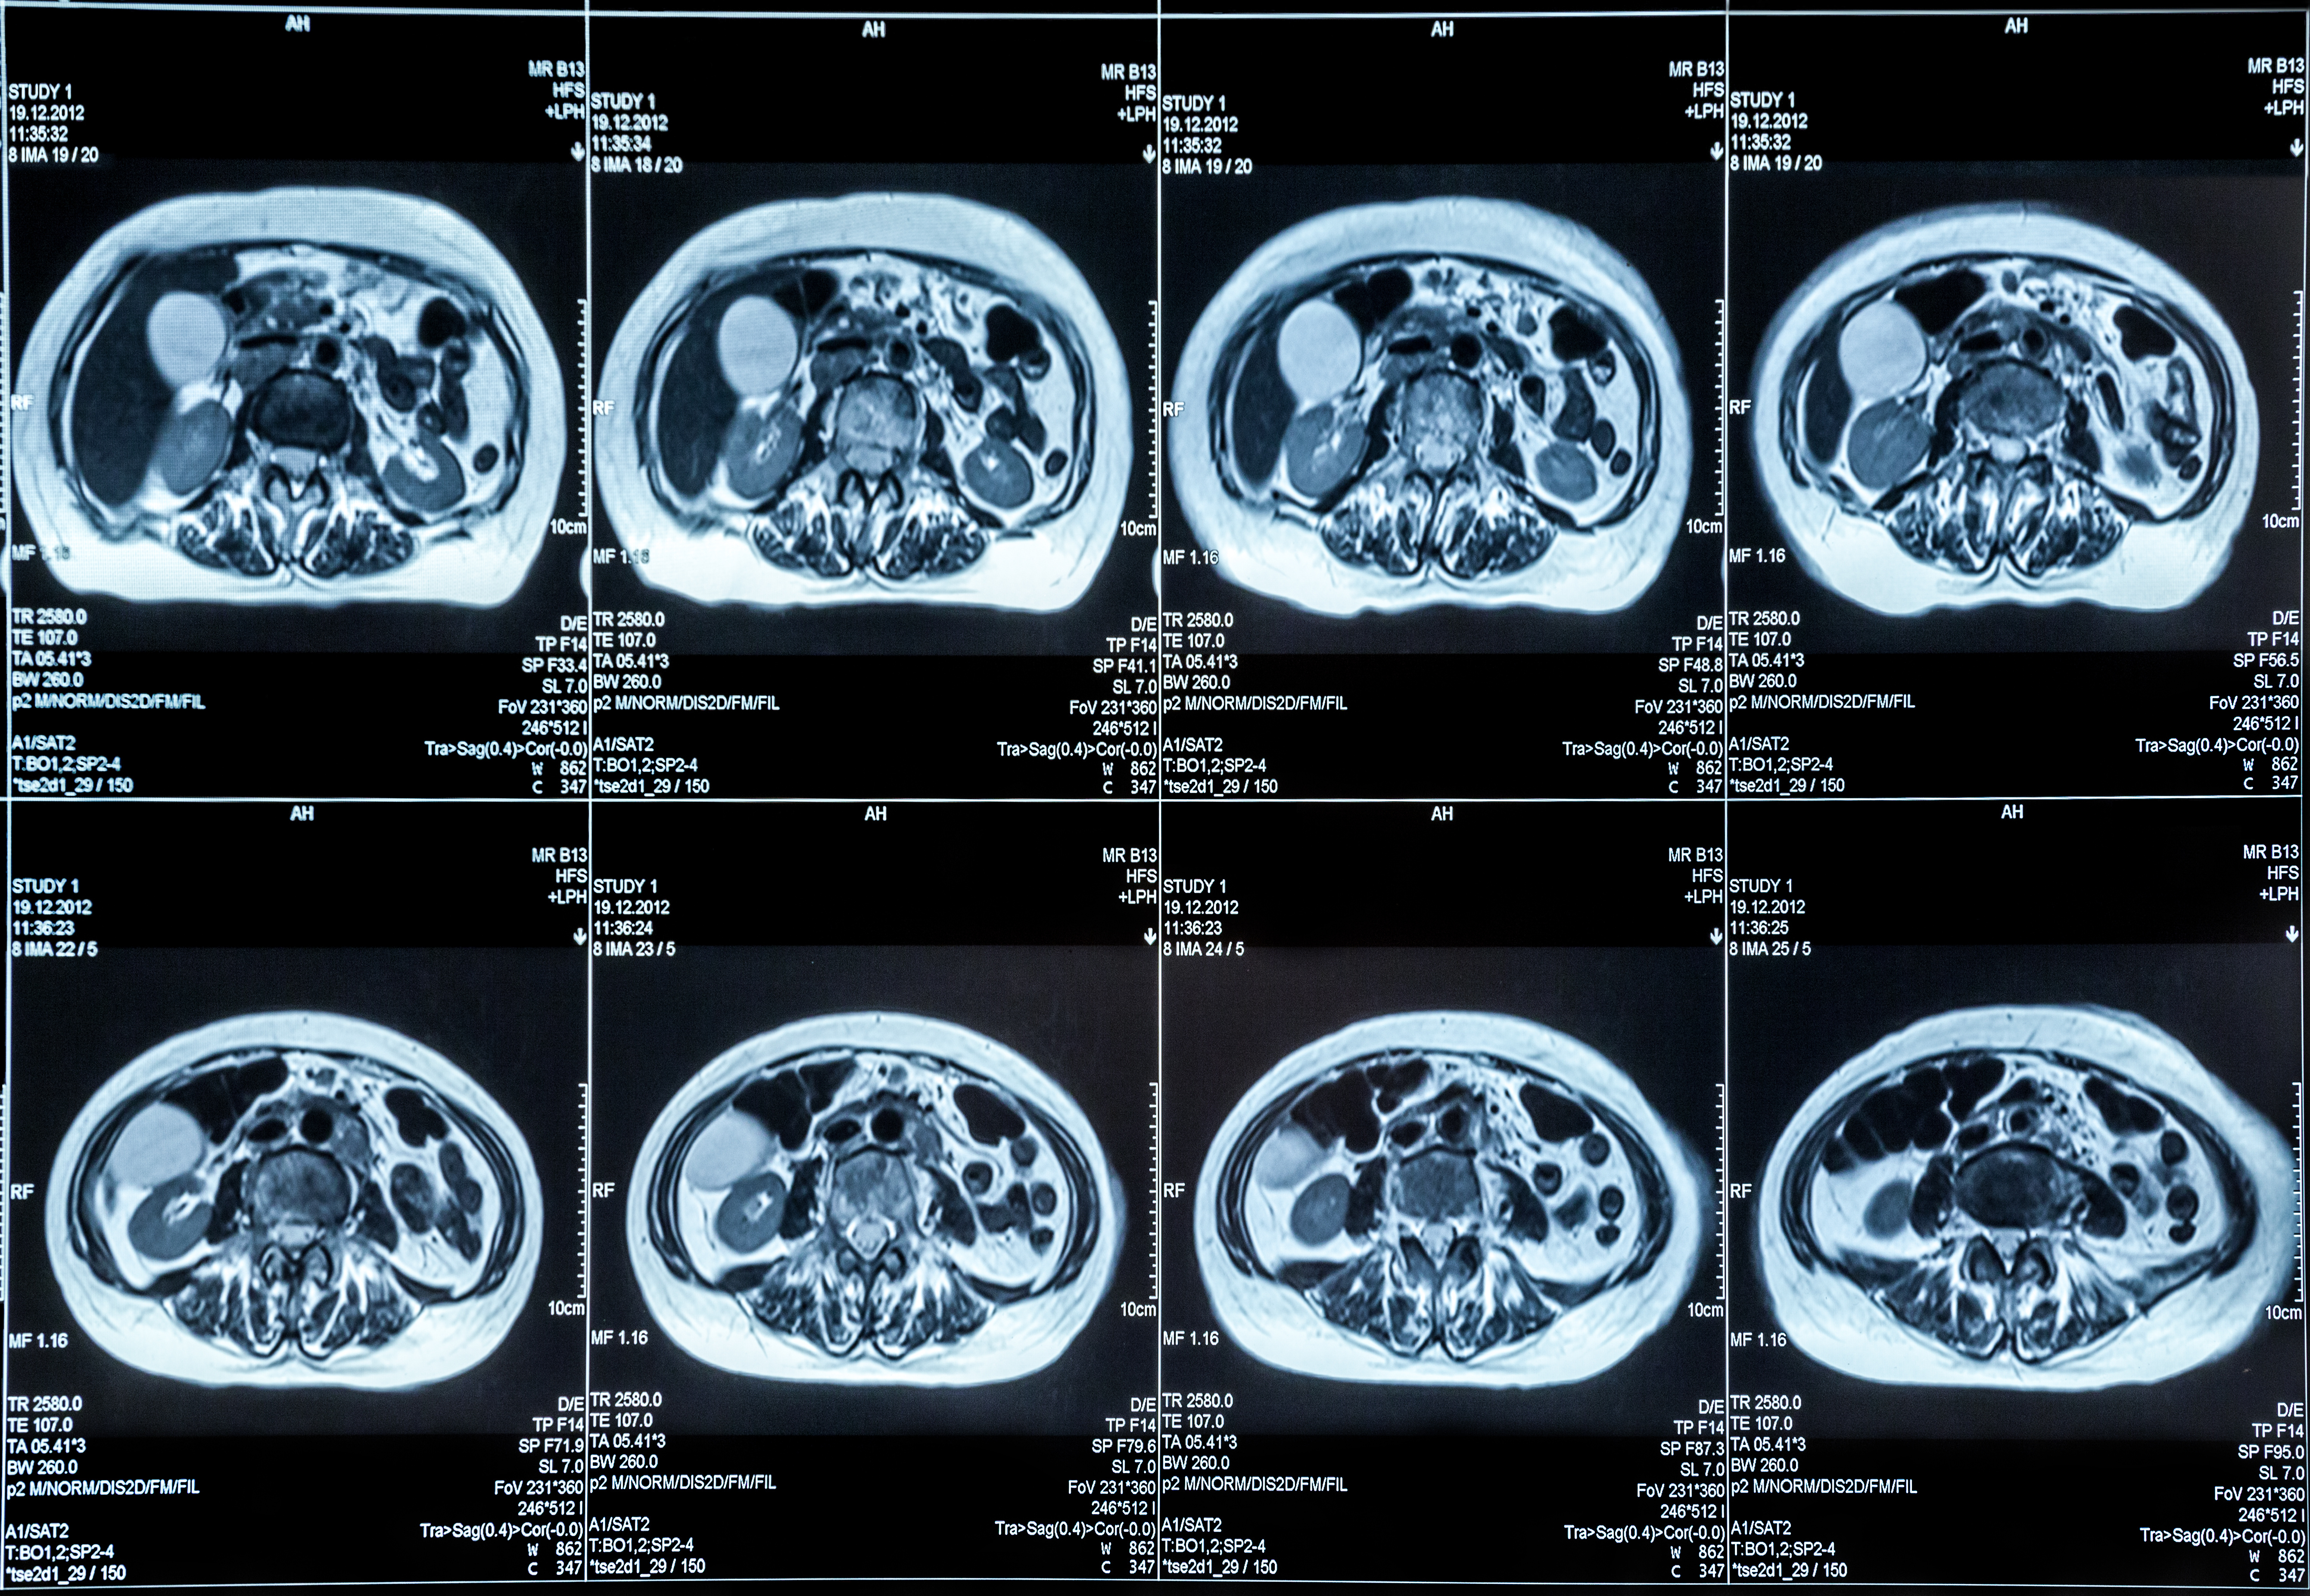

In a new study looking at pre-operative assessment of low-grade endometrial cancer, researchers found that while magnetic resonance imaging (MRI) had 20 percent higher specificity than transvaginal ultrasound for deep myometrial invasion, there was no difference in sensitivity.